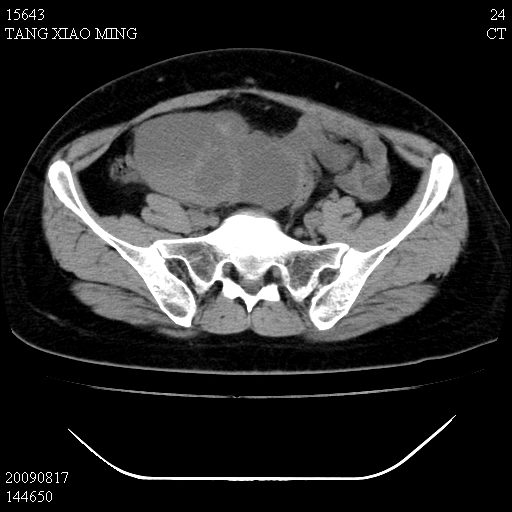

标题: CT21692:盆腔病变

女,33岁,右下腹痛2年余,既往宫外孕病史,如在我院手术,结果下周公布,

可能的诊断。1子宫内膜异位【子宫腺肌症并右卵巢巧克力囊肿】;2 右卵巢囊腺瘤。子宫肌瘤

1)考虑卵巢巧克力囊肿,不排除卵巢囊腺瘤。2)子宫肌瘤可能。

卵巢囊腺瘤,子宫肌瘤,直肠壁厚,不除外占位.